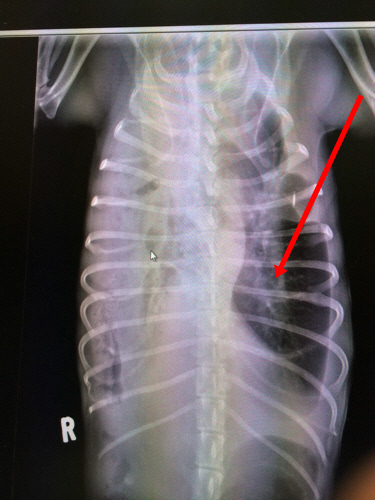

This is Daffodil's chest X-ray. The dark

place is where her intestines have crowded

into the space where her lung is supposed

to be, making it very difficult for her to

breath. She is critical.